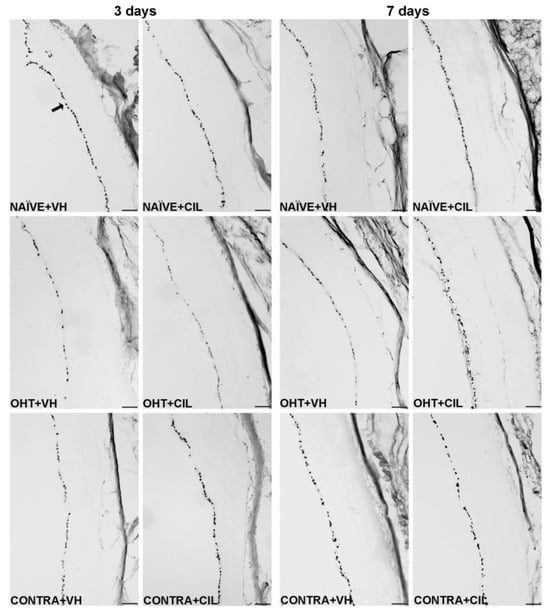

Figure 3. Brn3a + cell count in the total retina 3 and 7 days after surgery. Brn3a+ cells were measured in the left photocoagulated eye (laser-induced ocular hypertension, OHT), and its contralateral (CONTRA). Data also include a group of non-manipulated (NAÏVE) mice. Animals were administered cilastatin (CIL, 300 mg/kg, i.p.) or vehicle (VH, saline) daily two days before the surgery until sacrifice 3 or 7 days after OHT induction; i.e., animals received 6 or 10 injections, respectively. Microphotographs taken at 10× magnification show the main general results of the Brn3a (brain-specific homeobox/POU domain protein 3A) immunohistochemical assay of the different experimental groups 3 and 7 days after OHT induction. In the 3 days NAÏVE + VH microphotograph, an arrow pointing at a Brn3a+ retinal ganglion cell, located in the retinal ganglion cell layer, is included as an example. Scale bar: 50 μm.

2.2. Analysis of RGCs: Brn3a+ Expression

Results of Brn3a+ expression are shown in Figure 2 and Figure 3 and Table S1. In the whole retina, three days after the surgery, OHT induced a significant reduction in the number of Brn3a+ cells, as compared to both retinas from NAÏVE and CONTRA eyes; CIL administration did not affect Brn3a expression. Similar results were observed seven days after the surgery: a significant decrease in the number of Brn3a+ cells was observed in response to OHT (OHT + VH vs. NAÏVE + VH, p < 0.001), and a more subtle decrease was also observed in the CONTRA eyes (CONTRA + VH vs. NAÏVE + VH, p = 0.013). At this time point, CIL was able to prevent and/or revert OHT effects (OHT + CIL vs. OHT + VH, p = 0.012).

A further detailed regional analysis of the retina revealed that the decrease in Brn3a+ cells, previously described 3 days after the surgery, was quite homogeneously distributed, as gathered from Figure 2. The reduction in Brn3a+ cells seems to be more abrupt within the temporal retina (for statistical details, consult Table S1). No effects of the CIL treatment were revealed in this analysis, except for the temporal superior (T-S) area, where the decrease in the OHT + VH group could not be observed in the OHT + CIL mice.

Seven days after the surgery, the reduction in Brn3a+ cells seemed to be notably limited to more nasal and central retinal areas; OHT eyes presented a larger reduction in the number of Brn3a+ cells within the N-C, N-I and C-S areas of the retina. CIL was able to counteract the effects of OHT within these retinal regions, although statistical significance was only achieved in the C-S retina. Instead, the already reported reduction in Brn3a+ cells in the whole retina of CONTRA eyes appeared to reflect a deeper affection of the N-C and N-I regions of the retina (Figure 2; for statistical details, consult Table S1).

In the current study, we have analyzed the possible protective effects of CIL in the glaucomatous pathology. CIL returned the number of Brn3a+ cells in the OHT + CIL eyes to values closer to the NAÏVE ones mainly in the T-S area by day 3, and in N-C, N-I and C-S areas by day 7. CIL was also able to revert all the changes found in CONTRA eyes.